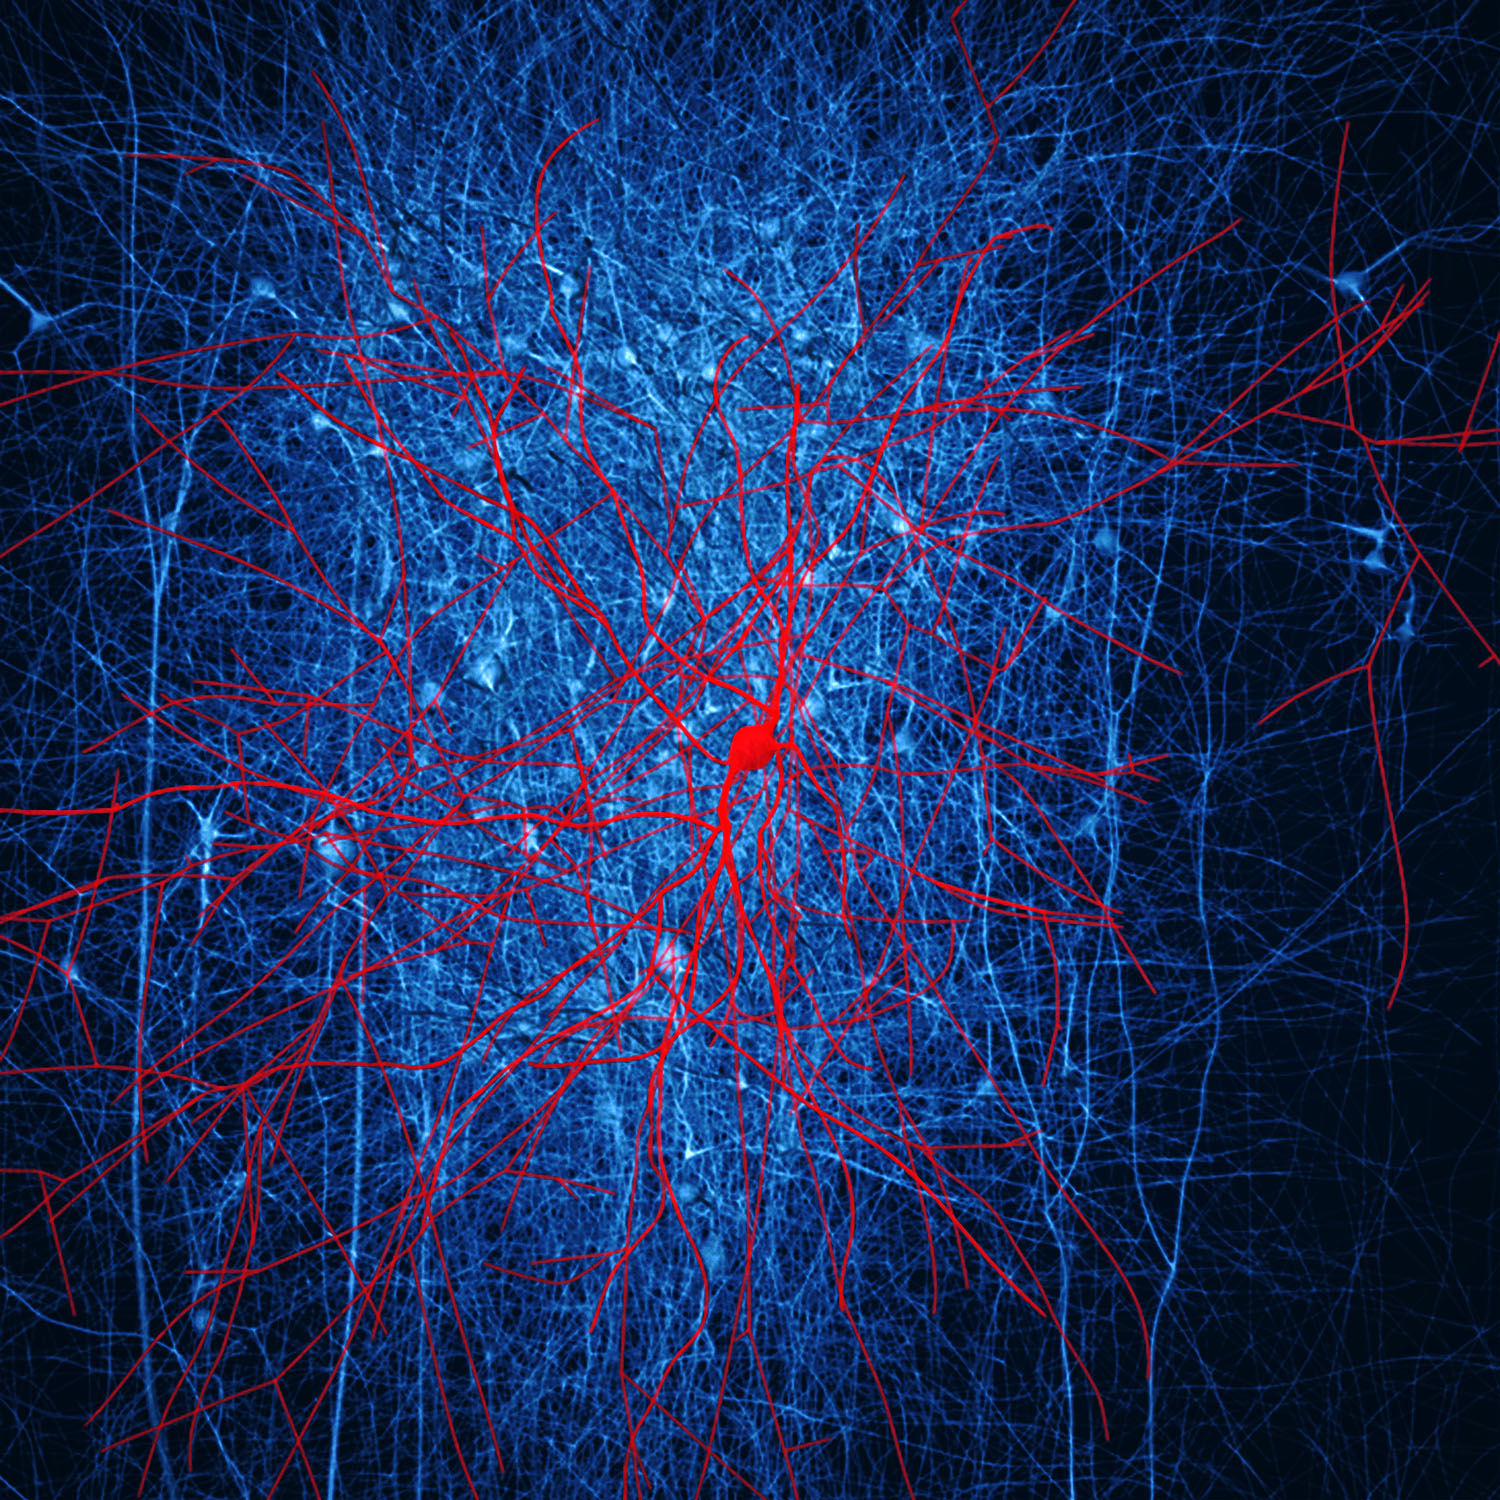

Used by permission.

The two glial cells above are a microglial cell (upper left) and an oligodendrocyte (center) from a human brain, via a flourescent light micrograph. Glial cells produce myelin; they are extremely important to brain function. The myelin coats the axons radiating from neurons, thereby enhancing more rapid communication of electrical impulses from one neuron to another. Microglia recognize and respond to areas of damage and inflammation in the central nervous system. The ragged extensions of the oligodendrocytes supply the myelin that insulates the axons.

The next image is not from a human brain, but is a computer simulation made by the Blue Brain Project. This project, several years old now, has been controversial from the start. The New York Times carried an article in 2013 (Requarth, see References) that gives a general description of the Blue Brain work.

The red-colored cell in this image is known as a basket cell. It is found in the molecular layers of the cerebellum, hippocampus, and cerebral cortex and is multipolar, which means that it connects to more than one neuron. Basket cells produce gamma-amino butyric acid, or GABA, which can inhibit (like a gatekeeper shutting the gate) the presynaptic neurons (blue-colored) from receiving messages. This isn't a positive or negative effect in itself; within one human being, in one moment, these effects can work to one's advantage or disadvantage.